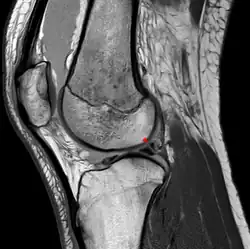

- das Ligamentum meniscofemorale posterius (auch Ligamentum Wrisberg) hinter dem hinteren Kreuzband und

- das Ligamentum meniscofemorale anterius (auch Ligamentum Humphry) vor dem hinteren Kreuzband verlaufend.[2][3][4]

In der MRT muss der Verlauf der Ligamenta meniscofemoralia berücksichtigt werden, um eine Verwechslung mit einem verlagerten Anteil des Außenmeniskus bei einem Riss desselben zu vermeiden.[10]